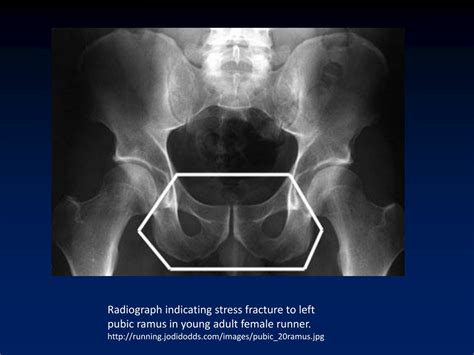

Diagnosing a Ramus Pubic Fracture involves a combination of physical examination and imaging tests. The diagnostic process typically includes:

• Physical Examination: A healthcare provider will assess the pelvic area for pain, swelling, and deformity.

• Imaging Tests: X-rays, CT scans, and MRI scans are commonly used to visualize the fracture and determine its extent.